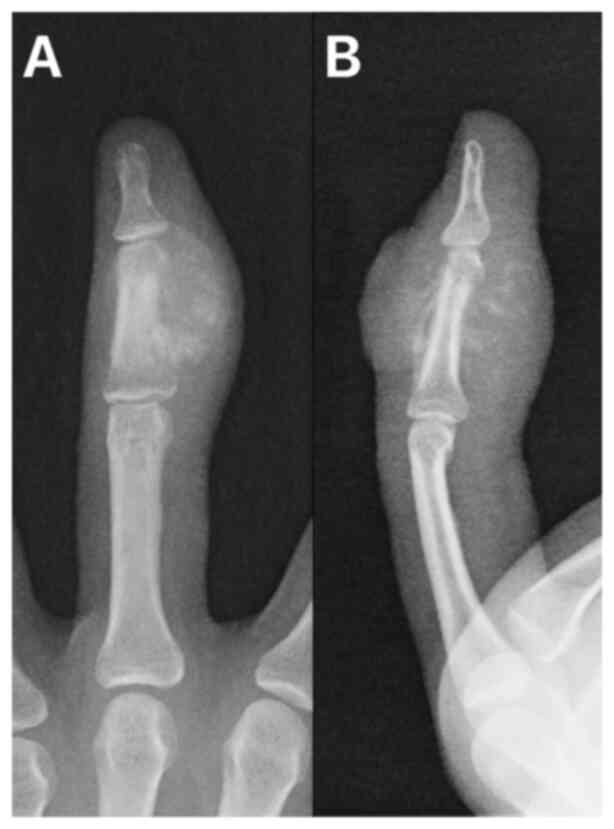

A 26-year-old female patient presented to a local surgical department in the Moravian-Silesian region with a 3-month history of persistent pain and swelling in the middle finger of their left hand. An incision was made under local anesthesia, but the lesion eventually ulcerated and in March 2018, the patient was referred to the Masaryk Memorial Cancer Institute Sarcoma Center (Brno, Czechia) for further evaluation. CT scans demonstrated an osteoblastic lesion in the middle phalanx (Fig. 2) and histopathology confirmed the diagnosis of high-grade parosteal osteosarcoma (Fig. 3). The Musculoskeletal Tumor Committee recommended resection of the third ray, which was performed successfully (Fig. 4). The final histopathology report indicated high-grade osteoblastic osteosarcoma and a complete resection (Fig. 5). Following the surgery, the patient underwent four cycles of the standard combination CHT regimen (10), comprising high-dose methotrexate (12 g/m2), doxorubicin (75 mg/m2) and cisplatin (120 mg/m2). However, due to toxicity, the regimen was interrupted. Treatment was then adjusted to two additional cycles of monotherapy, with doxorubicin reduced (50 mg/m2) and methotrexate continued at 12 g/m2. At follow-up examinations, the patient remained disease free. However, 5 years after the surgical procedure, the patient died due to a sudden cardiac arrest, which was potentially related to the cardiotoxic effects of the CHT.

Case 1. Radiographic images showing an osteoblastic lesion in the intermediate phalanx of the middle finger of the left hand. (A) Anteroposterior view and (B) lateral view.